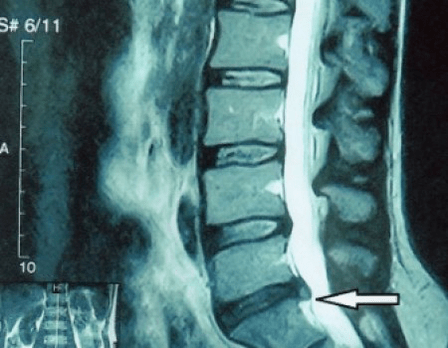

Trápaga bizkarrezurraren "X izpi" batek, eta flexio eta luzapenerako proba funtzionalak eginda ere, ez du kartilagorik erakusten, haien ehunak X izpiak transmititzen baititu. Hala eta guztiz ere, ornoen kokapenaren arabera, orno arteko diskoen altuerari buruzko ondorio orokorrak atera daitezke, lepoaren kurbadura fisiologikoaren zuzenketa orokorra - lordosia, baita ornoetan hazkuntza marjinalak egoteaz gainazaleko narritadura luzea duten orno arteko disko hauskor eta deshidratatuek. Proba funtzionalek ezegonkortasunaren diagnostikoa berretsi dezakete zerbikal bizkarrezurra.

Diskoak beraiek CT edo MRI erabiliz soilik ikus daitezkeenez, erresonantzia magnetikoa eta X izpien konputazio bidezko tomografia adierazten dira kartilagoen barne egitura eta irtenguneak eta herniak bezalako formazioak argitzeko. Horrela, metodo hauen laguntzaz, diagnostikoa zehatz-mehatz egiten da, eta tomografiaren emaitza neurokirurgia sailean hernia baten tratamendu kirurgikorako indikazio bat da, baita gaurkotasun gida ere.